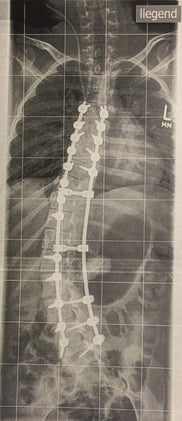

Es werden Fotos und Röntgenaufnahmen gezeigt.

Es folgen eine lange Reihe von sehr eindrucksvollen Fotos, Röntgenbilder, Vorher-Nachher-Bilder.

Ausgangsituation

nach Korrektur

von der Seite gesehen